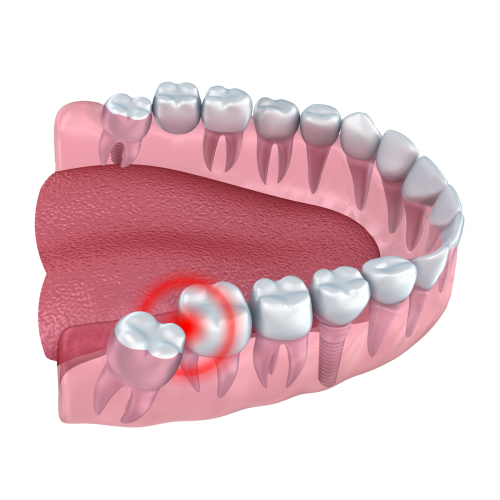

Serious dental risks you face when leaving wisdom teeth untreated today A Wisdom Tooth may seem harmless at first, but improperly erupted wisdom teeth can ...

Serious dental risks you face when leaving wisdom teeth untreated today A Wisdom Tooth may seem harmless at first, but improperly erupted wisdom teeth can lead ...